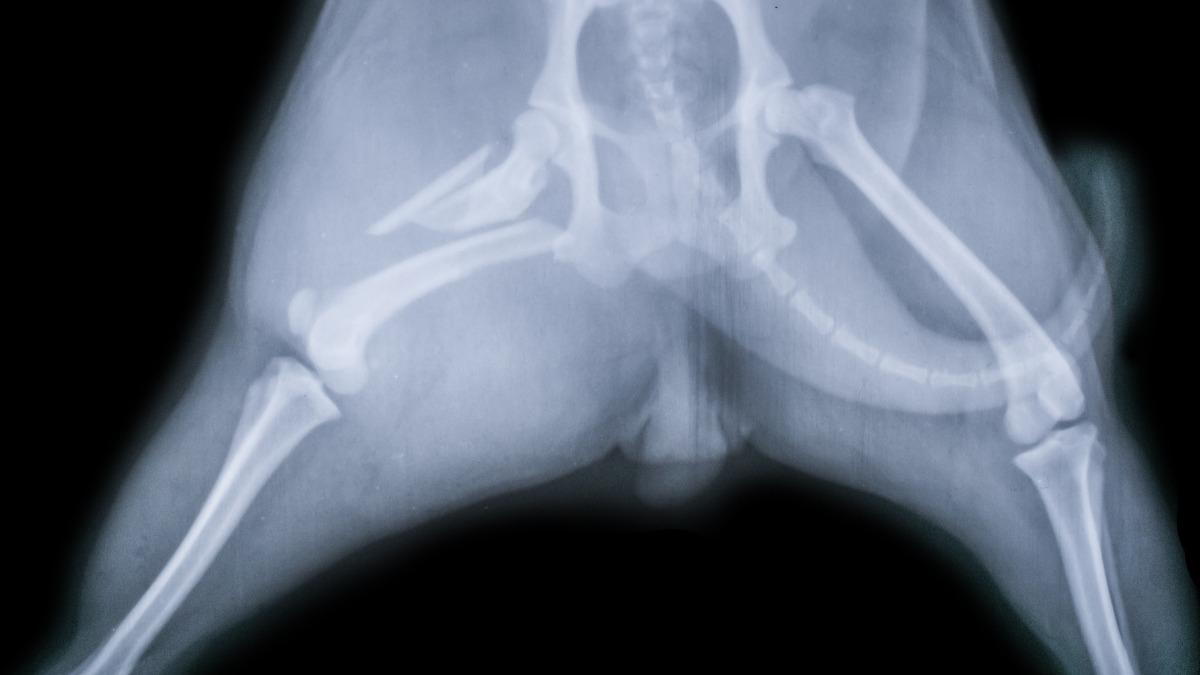

Veterinary X-rays are a valuable tool for diagnosing conditions that aren’t visible during a routine exam. At Ashworth Road Animal Hospital in West Des Moines, IA, we use digital X-rays to identify issues like broken bones, swallowed objects, joint problems, or internal organ abnormalities. Our clinic relies on X-rays to give us a clearer picture of what’s happening inside your pet’s body. It allows our veterinarians to make more accurate diagnoses and begin the right treatment without delay.

If your pet suddenly starts limping or has trouble climbing stairs, jumping, or standing up, it could point to a bone or joint problem. These symptoms often require an X-ray to determine if there is a fracture, arthritis, or another orthopedic condition. Delaying imaging in these cases can make a condition worse or more difficult to treat. Our clinic recommends early evaluation for any persistent mobility change.

Frequent vomiting, difficulty breathing, or persistent coughing may signal a deeper issue involving the lungs, heart, abdomen, or digestive tract. A digital X-ray can reveal foreign objects, enlarged heart, fluid buildup, or other irregularities affecting your pet’s organs. These problems are not always visible through observation alone, so imaging is key to finding and treating the root cause quickly.

If your pet has been hit by a car, fallen from a height, or experienced any trauma, even if they seem fine, an X-ray is often recommended. Some injuries don’t show up immediately but can worsen over time. Our clinic uses X-ray treatment to screen for internal injuries or broken bones after any serious incident. It’s better to be safe and catch problems early.